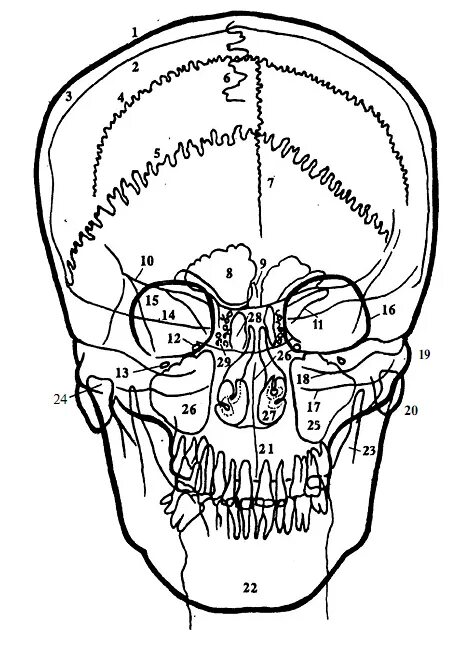

Череп проекции